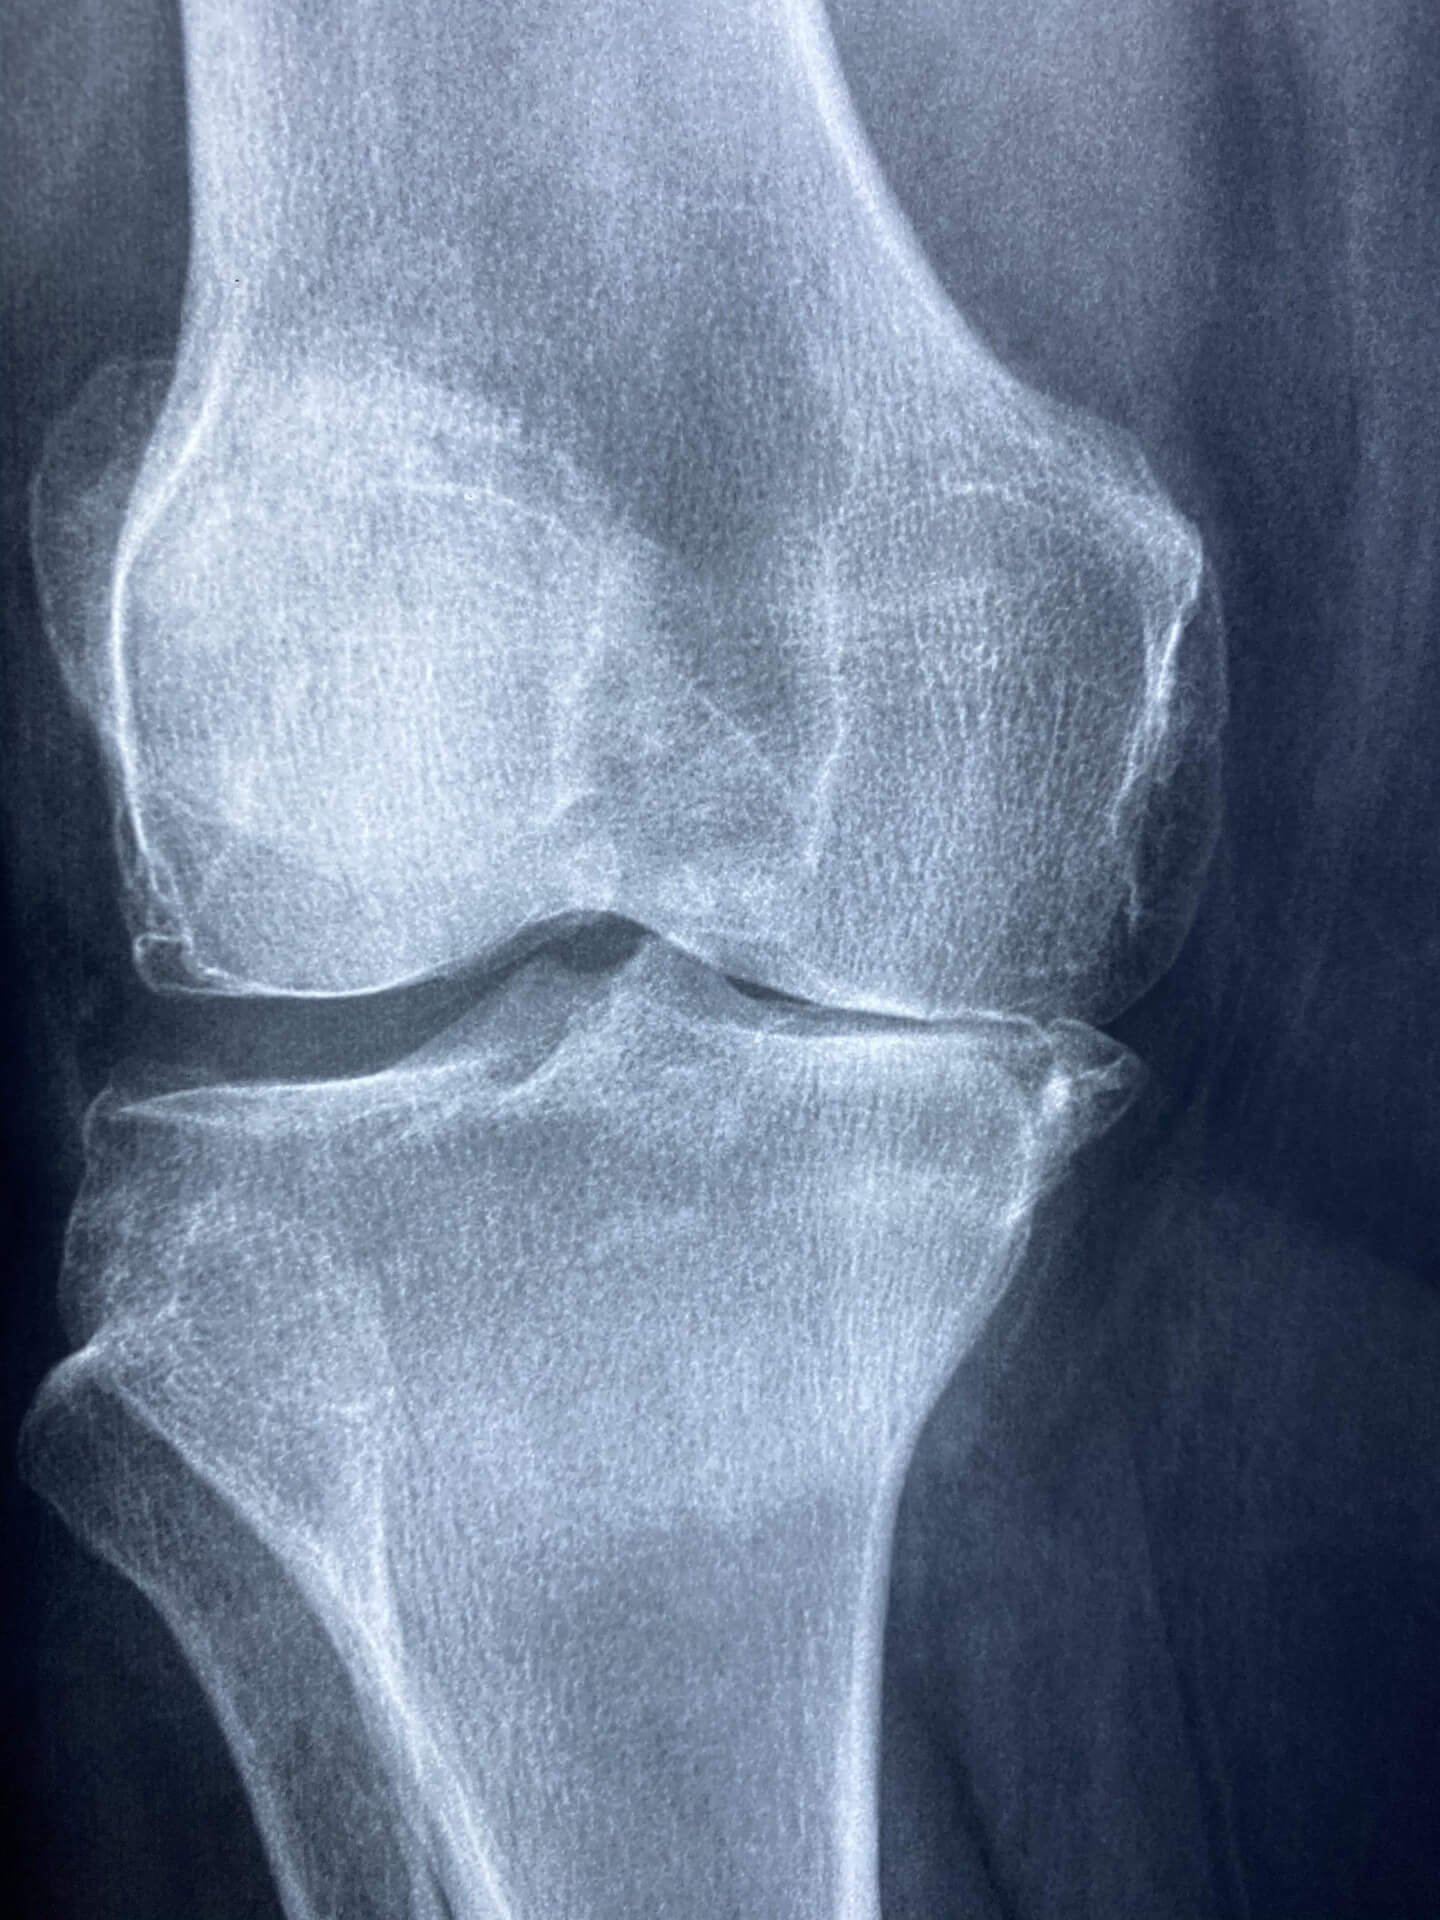

관절염은 노화, 체중 증가, 잘못된 생활습관 등 다양한 요인으로 인해 발생하는 대표적인 근골격계 질환입니다. 하지만 꾸준한 관절염 완화 운동은 통증을 줄이고 관절의 움직임을 개선하는 데 매우 효과적입니다. 특히 스트레칭, 수중 운동, 저강도 근력 운동 등은 관절에 무리를 주지 않으면서도 근육을 강화해줍니다.

본 글에서는 의학적 근거를 바탕으로 무릎 관절염 환자에게 도움이 되는 대표 운동법과 주의사항을 구체적으로 정리했습니다. 매일 20분씩만 실천해도 통증 완화와 관절 기능 개선을 경험할 수 있습니다. 지금부터 자세히 알아보겠습니다.

관절염 완화 운동은 염증으로 인해 굳어진 관절의 움직임을 부드럽게 하고, 근육을 강화하여 통증을 줄이는 운동을 의미합니다. 특히 무릎 관절염이나 손가락 관절염 환자에게 효과적인 운동법은 의학적으로도 검증되어 있습니다.

관절염은 유전, 노화, 비만, 잘못된 자세 등이 주요 원인입니다. 증상은 부기, 열감, 운동 시 통증 등으로 시작해 점점 관절 변형으로 이어질 수 있습니다.

최근 연구에 따르면, 꾸준한 관절염 완화 운동은 염증 물질 생성을 줄이고 연골을 보호하는 데 긍정적인 영향을 줍니다. 이는 약물치료만으로는 얻기 어려운 장기적인 개선 효과를 제공합니다.